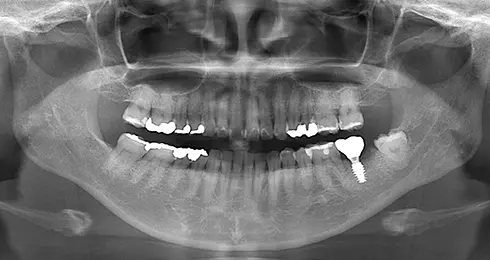

CASE

| 年齢/性別 | 40代女性 |

| 主訴 | 右上の詰め物が取れた |

| 治療内容 | 歯周病とむし歯の治療を目的に来院。左下の奥歯は根の状態が悪く、病変も大きかったため保存が困難と判断。 インプラント治療を実施しました。 |

| 治療期間 | 4か月 |

| 費用 | 566,500円税込 |

| リスク・副作用 | 炎症反応によって術後に腫れが生じることがあります。その程度は、手術の範囲や方法によって異なりますが、多くの場合、時間の経過とともに徐々に治まります。 ごく稀に、下顎奥歯の外科手術後に、唇や顎に痺れを感じることがあります。 |